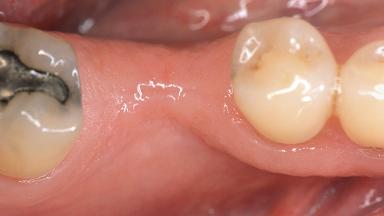

Soft-Tissue Volume Augmentation Using a Connective-Tissue Graft Harvested from the Maxillary Tuberosity

| Jaw | Mandible |

| Area | Posterior |

| # of Teeth | 1 |

| # of Implants | 1 |